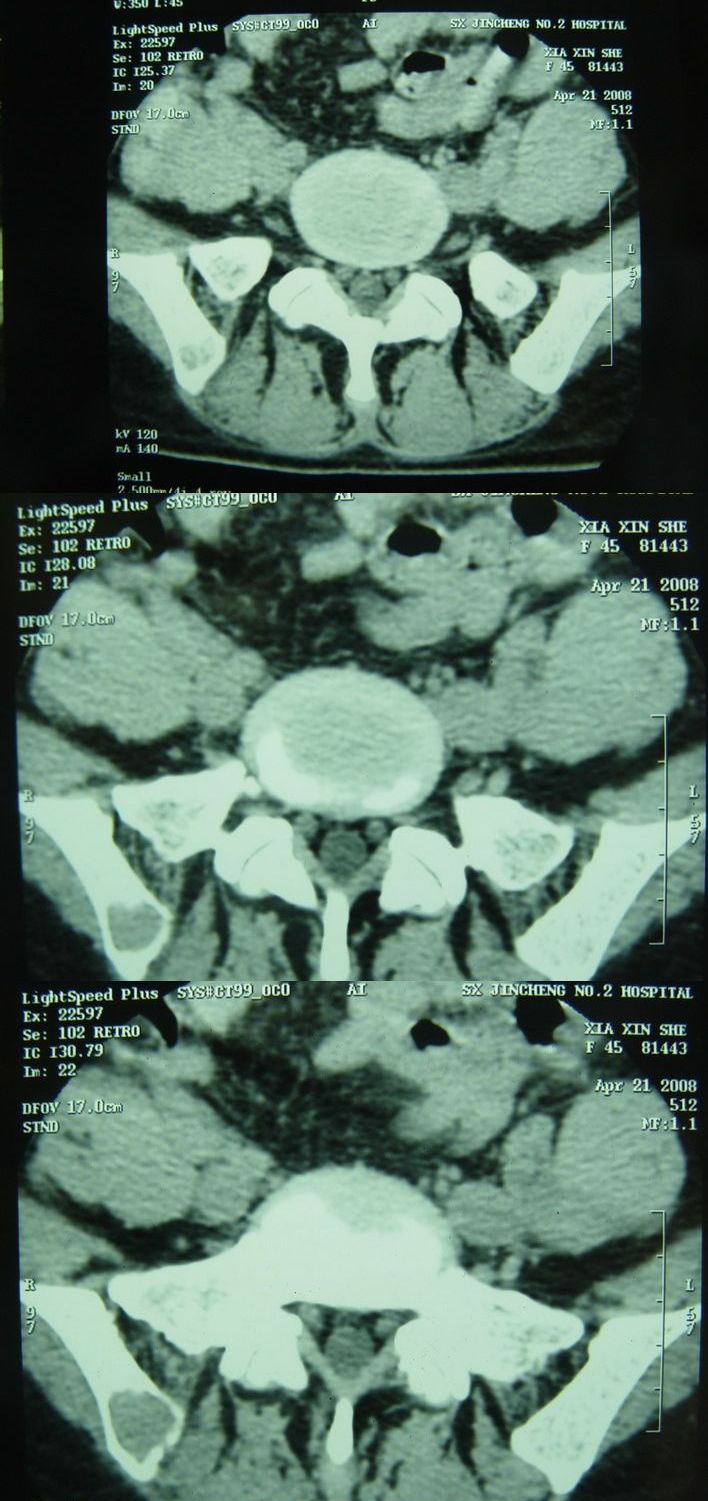

标题: CT13002:女,46岁。有子宫肌瘤手术史,现在出现右臀部向腿 [打印本页]

标题: CT13002:女,46岁。有子宫肌瘤手术史,现在出现右臀部向腿

右髂骨见一类圆形略高密度区,似见分层,骨质破坏不明显

考虑良性病变,以动脉瘤样骨囊肿可能性大

右侧髂骨后缘囊状膨胀性骨质改变,无明显骨间隔,周围无明显硬化及骨膜反应,周围软组织无异常,相邻骨组织密度增高,考虑:动脉瘤样骨囊肿可能,要注意与骨巨细胞瘤及转移瘤鉴别。

该病人今天做了增强,右侧髂骨病灶明显强化。

临床和影像学表现:女性患者46岁,有子宫肌瘤手术病史。影像所见可见残余宫颈部分,左右附件未见新生物;右髂骨翼后端囊状膨胀性骨破坏,囊性部分感觉有强化(楼主标上增强前后的ct值就很好了),未见明确的液—液平面,周边硬化不明显或轻度硬化。

分析:患者年龄46岁,没有明确外伤病史,病变呈膨胀性骨破坏,囊性部分未见明确的液—液平面,周边硬化不明显。综合分析该病例比较符合骨巨细胞瘤,不太符合动脉瘤样骨囊肿。

诊断:1、首先考虑骨巨细胞瘤;2子宫肌瘤术后改变